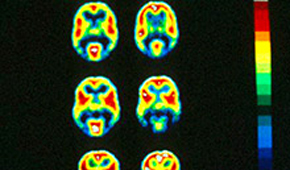

Все больше исследователей изучают то, как различные химические вещества в мозге влияют на процесс формирования зависимостей. Ученые из Университета Виктории в Новой Зеландии выяснили: судя по всему, некоторые становятся наркоманами из-за низкого уровня серотонина, вещества, связанного с настроением, пишет Zee News.

Уровень серотонина во время первого приема наркотика определяет то, станет ли человек зависимым. Люди с высоким уровнем серотонина становятся наркоманами гораздо реже. По мнению исследователей, их открытие приведет к созданию лекарств, предотвращающих развитие зависимости.

После того, как употребление наркотиков становится более частым, влияние серотонина ослабевает. На этом этапе продолжать принимать наркотики людей заставляет другое химическое вещество - дофамин. Он связан с наградой и поиском удовольствий. Если вовремя повысить уровень серотонина с помощью лекарственных препаратов, вероятно, возникновения зависимости удастся избежать.